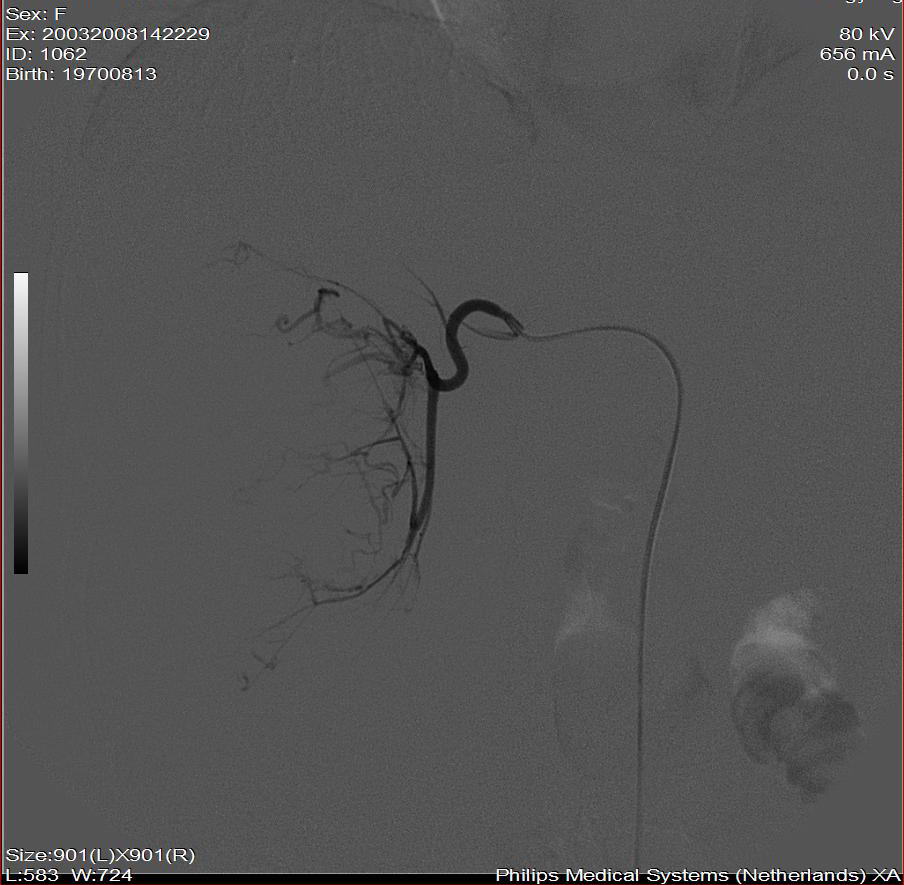

标题: DSA0138:F38Y,肝脏病变

巨块型肝癌介入术后,肝左叶有转移吗(第二次进行肝左动脉栓塞了吗?)

好牛的,右肝动脉发自肠系膜上动脉,不用微导管分次进行末梢栓塞,肿瘤染色完整。再次学习了。